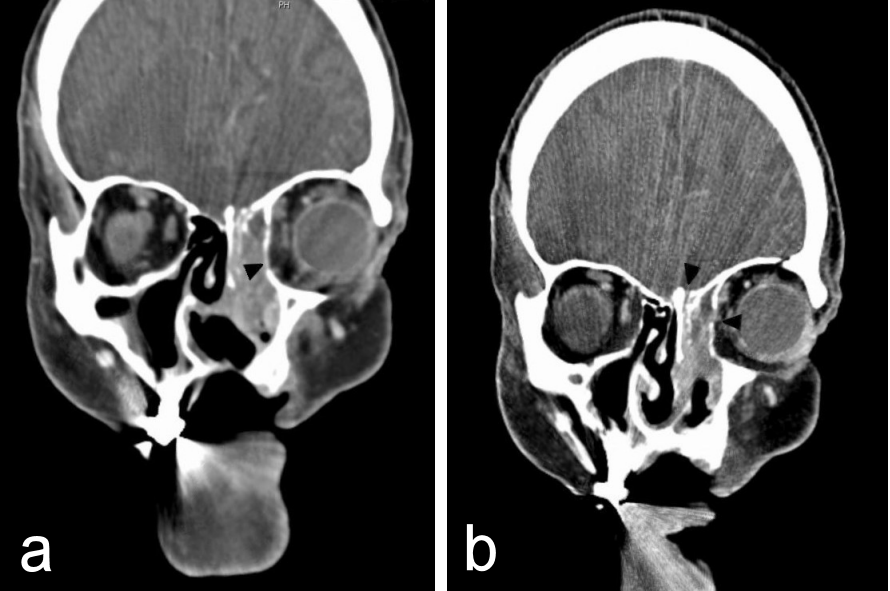

Clinical examination, anterior rhinoscopy and endoscopy revealed purulent secretions and a papilloma-like tumor occupying and obstructing the entire left nasal cavity, and proptosis of the left eye. There was no diplopia, cranial nerve palsy nor palpable cervical lymphadenopathy. Since recurrent IP was suspected, the patient was elected to computed tomogram (CT) of the head and neck area, which showed a heterogeneous opacification of an expansile mass in the left nose and the ethmoid sinus. The medial orbital wall, the anterior wall of the sphenoid sinus and the roof of the left ethmoid sinus were eroded with protrusion of the mass to the left orbit. Nasal septal perforation due to prior endonasal resections was also observed (Figure 1 [Fig. 1] and Figure 2 [Fig. 2]).